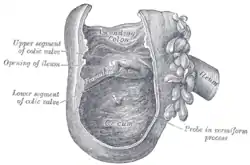

Interior of the cecum and lower end of ascending colon with the ileocecal valve labeled as "colic valve" | |

Ileum, cecum and ascending colon

Ileum, cecum and ascending colon Cecum and ileum